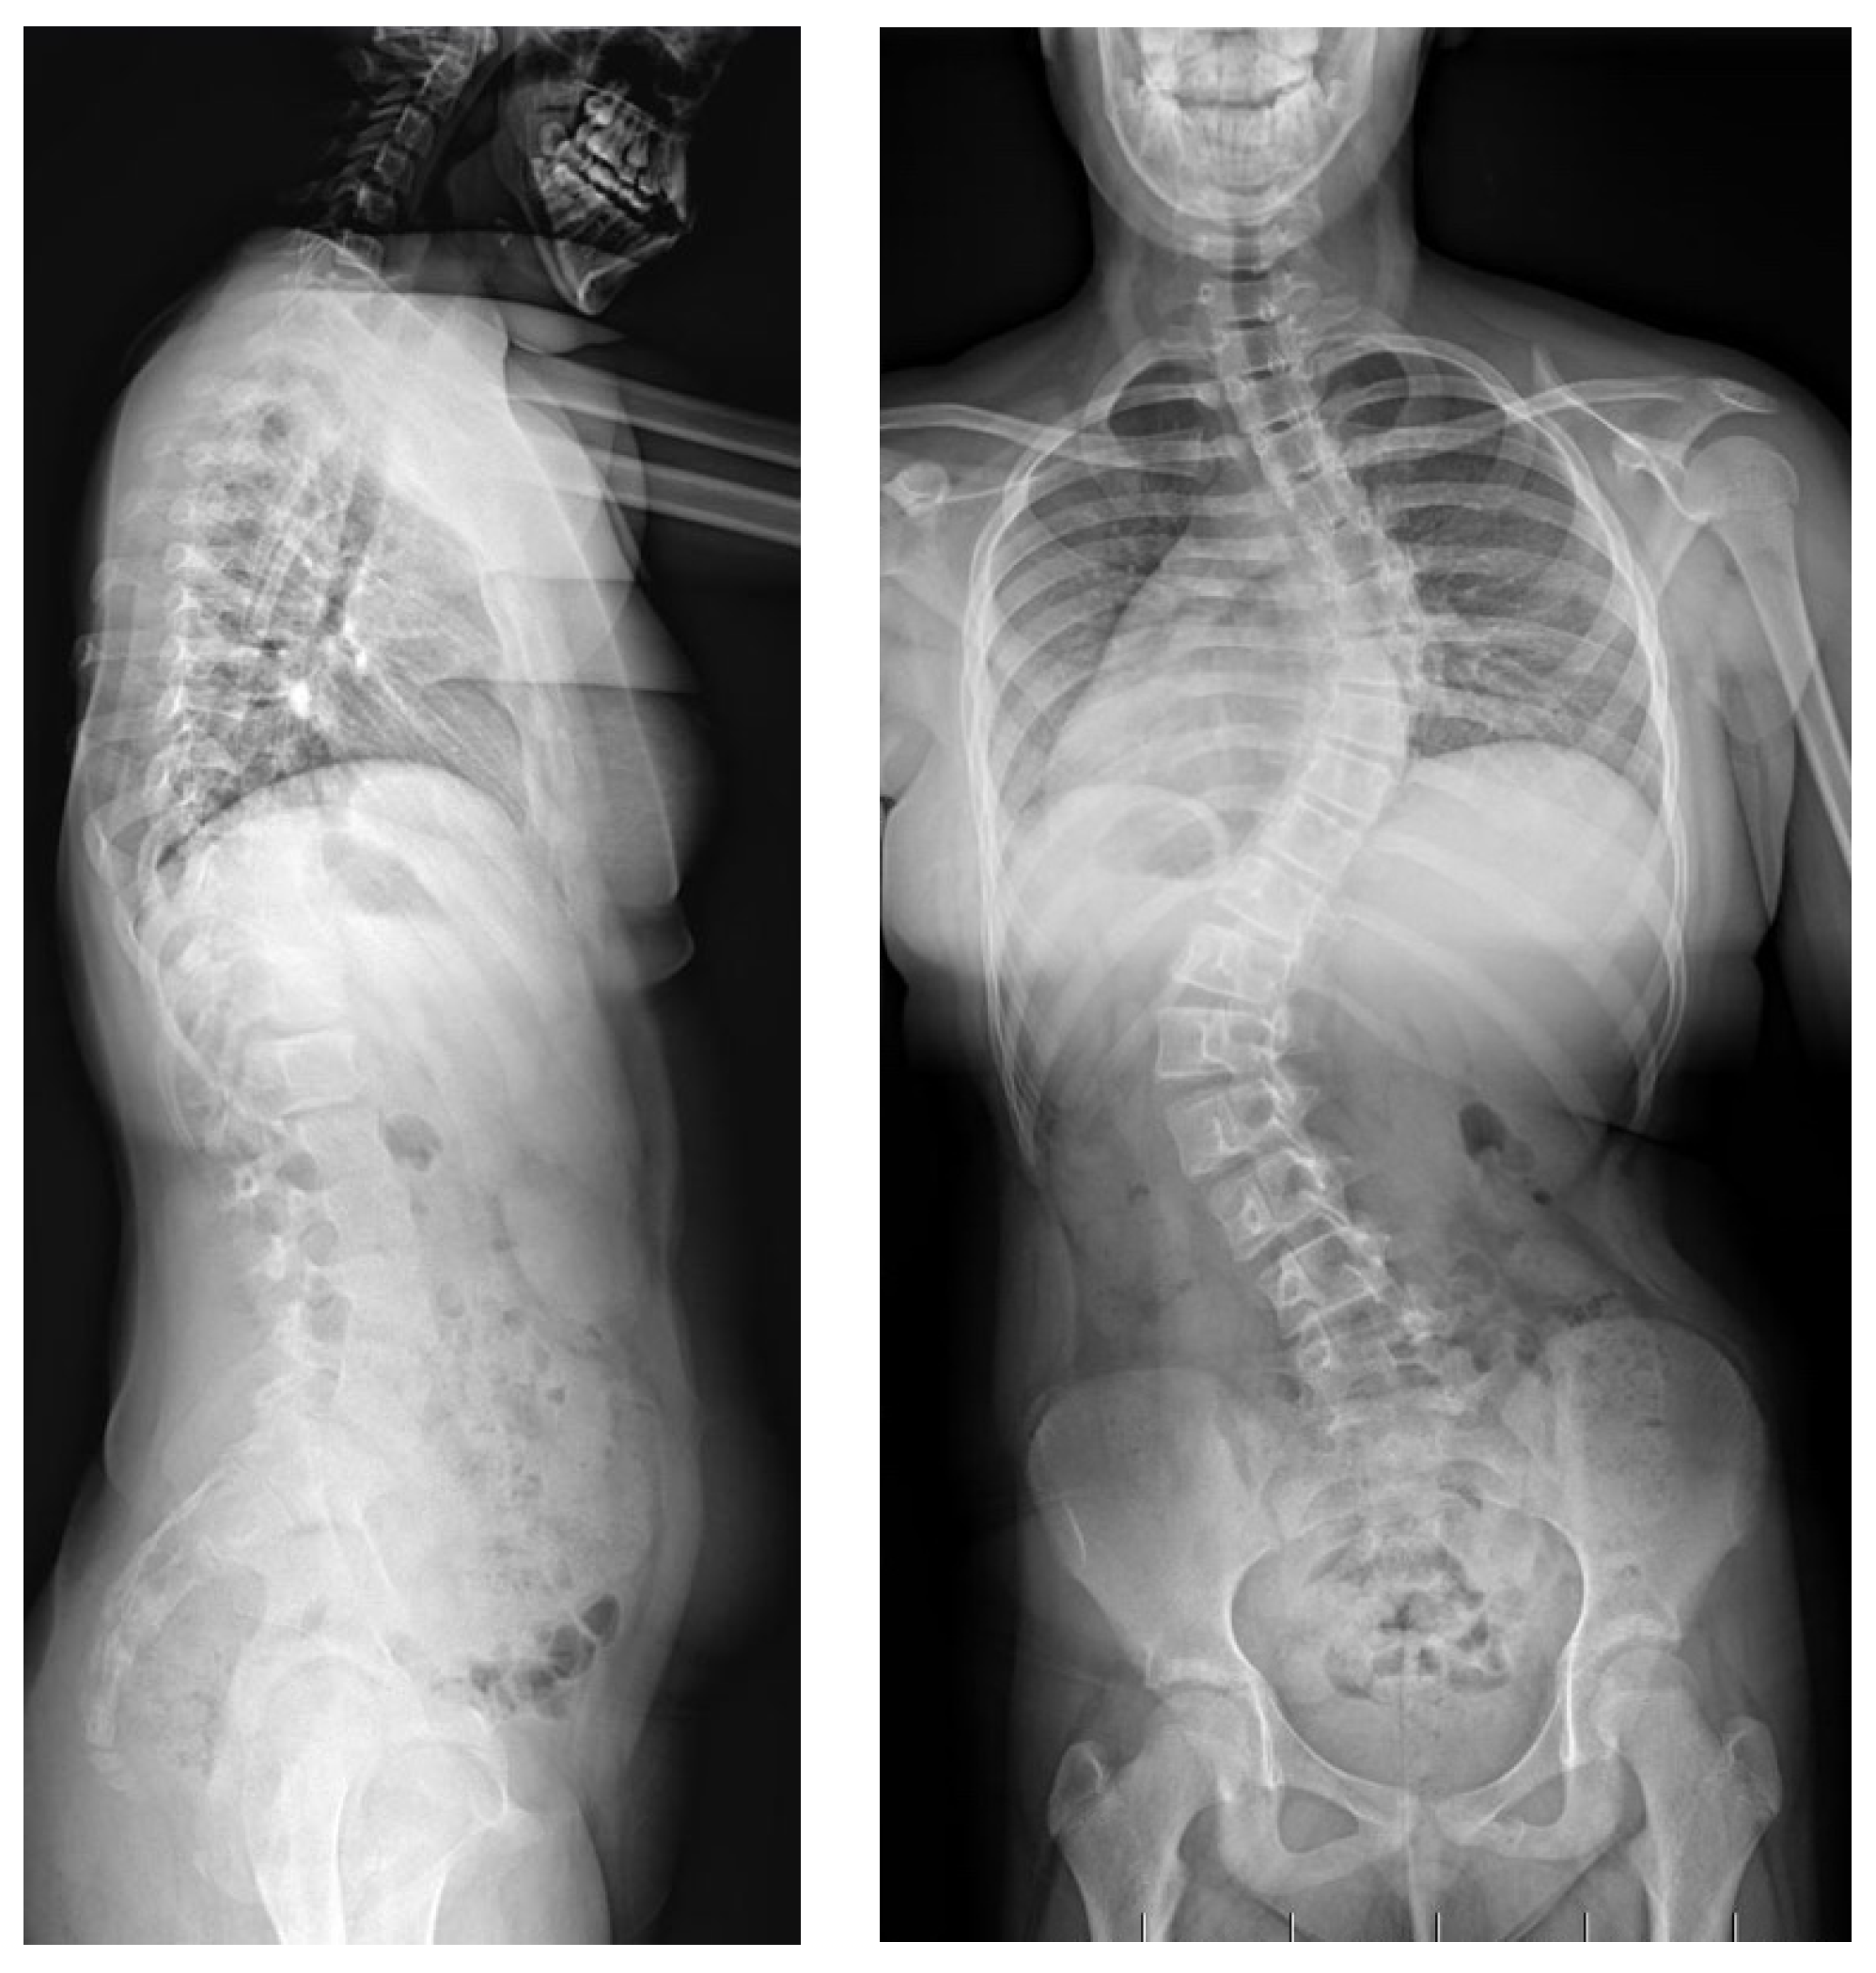

2.2. Example of Early-Onset Idiopathic Scoliosis

2.3. Example of Congenital Kyphosis